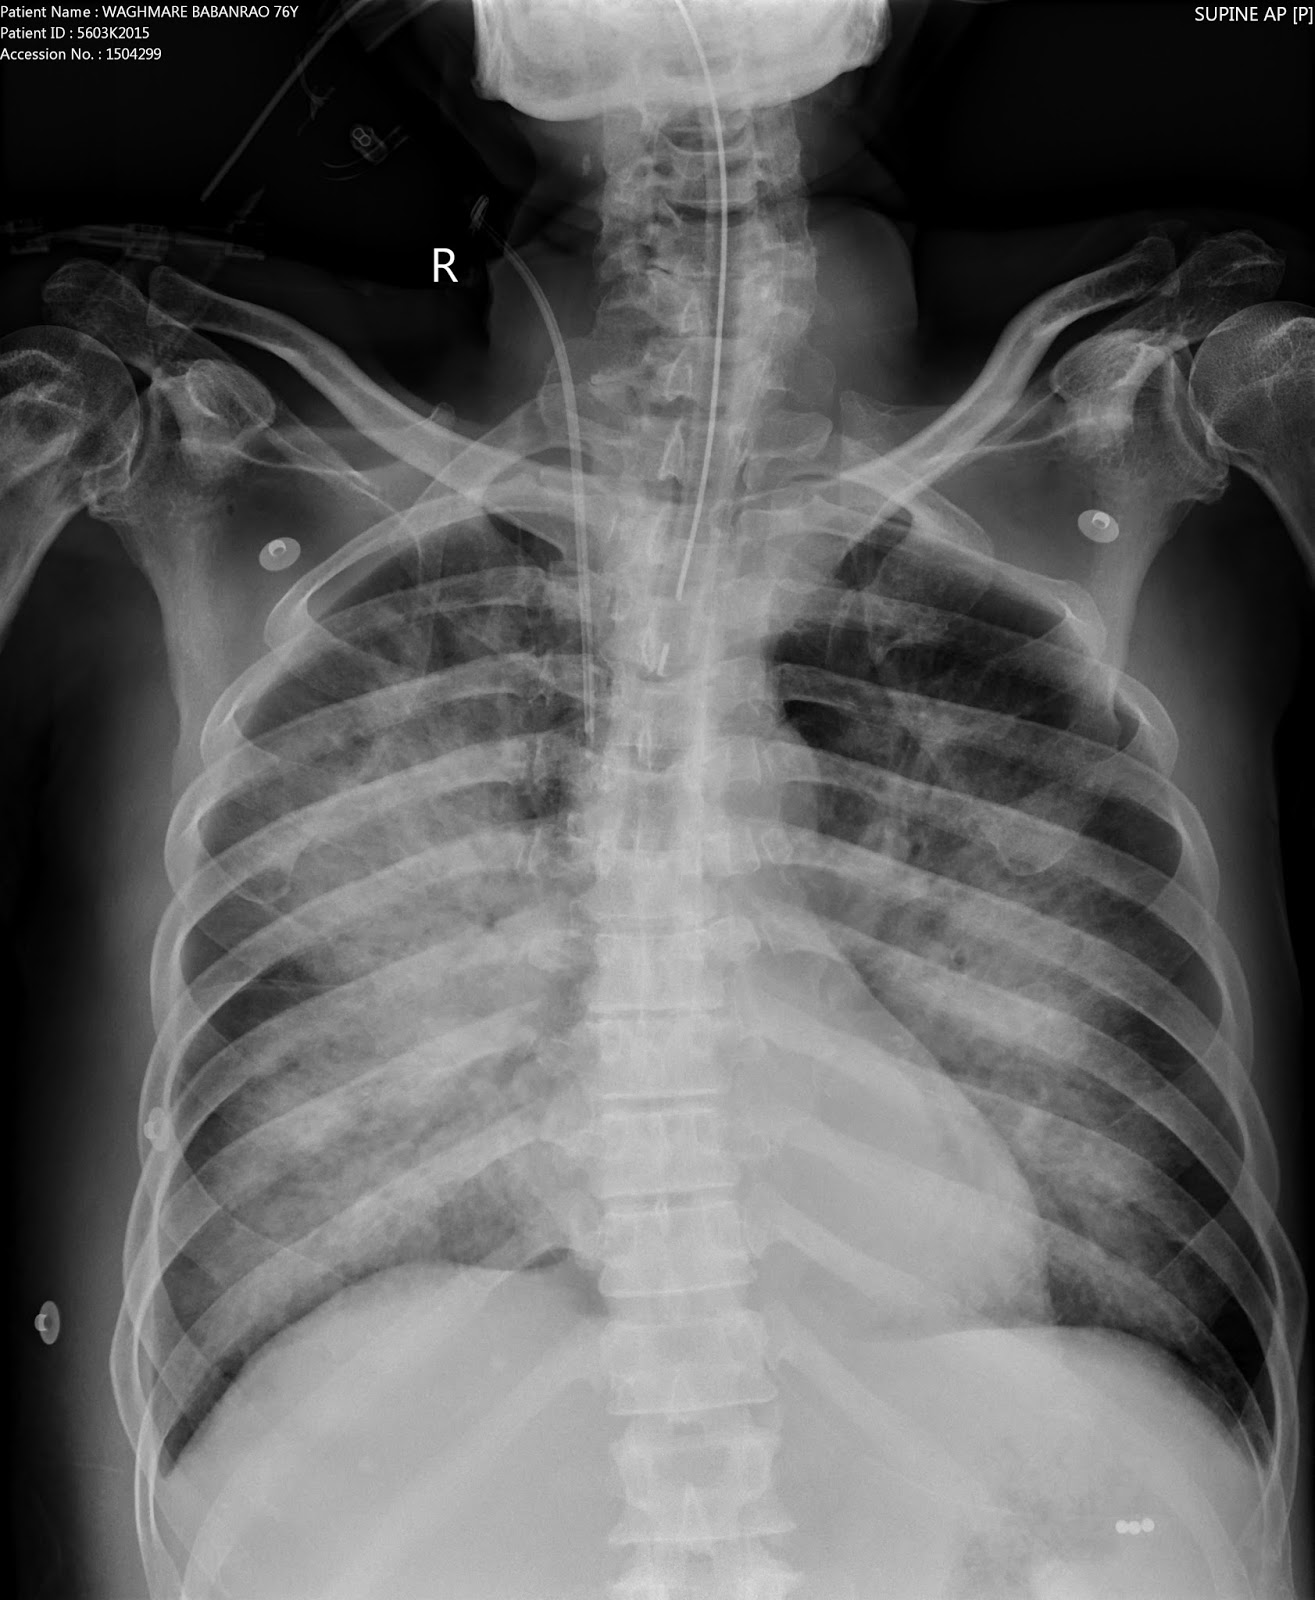

MCU study reveals-

| No filling defect within the bladder |

| filling defect at left VUJ with reflux on voiding |

| filling defect is better appreciated in partially distended bladder than with complete distension |

| UB with a cystic lesion |

| dialated terminal portion of left ureter |